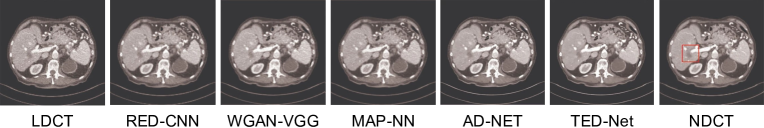

Refer to caption

Figure 11: Segmentation results on the Synapse dataset [256] using UNet, TransUNet [193], and ST-Unet [376].